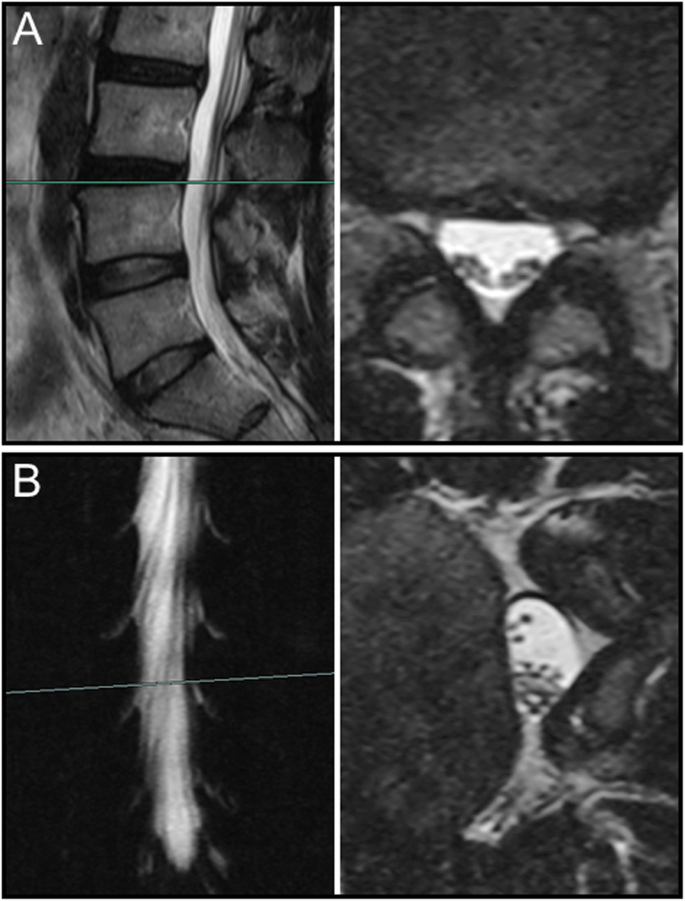

The sedimentation of nerve roots on MR images of various body position

Overall, nerve roots of 48 (85.7%) patients subsided to the ventral side of the dural sac on the prone MR images, although that of 8 (14.3%) patients remain stay in the dorsal side of dural sac. Of the 25 patients with a negative SedSign on supine MR images, the nerve roots settled to the ventral side of the dural sac on prone MR images in 24 patients (Fig. 1). Nerve roots in the remaining 1 patient, who was diagnosed as disc herniation, did not settle to the ventral dural sac (Fig. 2). For all the 31 patients with a positive SedSign, nerve roots subsided to the ventral side of the dural sac on the prone MR images in 24 patients (Table 2, Fig. 3). The nerve roots of the other 7 patients still stay (sequester) in the dorsal dural sac, which were due to single level (Fig. 4) or multiple level stenosis (Fig. 5). The nerve roots in patients with positive SedSign were more likely to stay in the dorsal dural sac on prone position MR images (22.6% vs 4%, P < 0.05, Table 2). In addition, the nerve roots subsided to the left dural sac in all the 5 patients when they were MR imaged on a left lateral position (Fig. 6).

The mechanism underlying nerve roots floating in the spinal canal against gravity remains unclear. We postulated that such an integrated force against gravity may result from multiple factors, including the length and tension of the nerve roots, the level of spinal stenosis, and the degree of lumbar lordosis. Alterations of these factors, as we clearly see, typically occurred in presence of degenerative changes in lumbar spine. In this study, positive SedSign on prone position MR images occurred mostly in multiple level spinal stenosis. In addition, the nerve roots in those case were tensioned (Fig. 5), which was also observed in the case with negative SedSign (Fig. 2). However, nerve roots did not subside in the direction of gravity despite loosen nerve roots in redundancy (Fig. 4). The role of tension in nerve roots sedimentation can be further studied using patients whose nerve roots tension is high, such as tethered spinal cord syndrome.